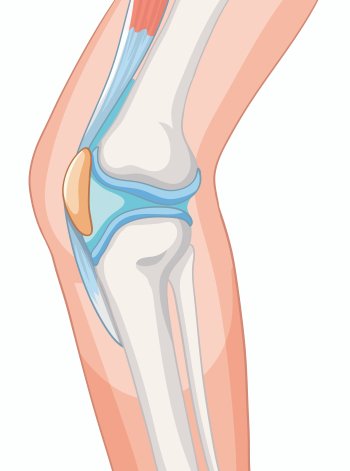

We are pleased to introduce Astha Hospital, the Best Multi-speciality Hospital in Chikali, offering world-class healthcare services to the communities of Moshi, Bhosari, and Pimpri Chinchwad, Pune. Our 50-bed, state-of-the-art tertiary care center provides comprehensive specialty and super-specialty treatments in Orthopaedics, Gynecology, Spine, Trauma, and Critical Care.